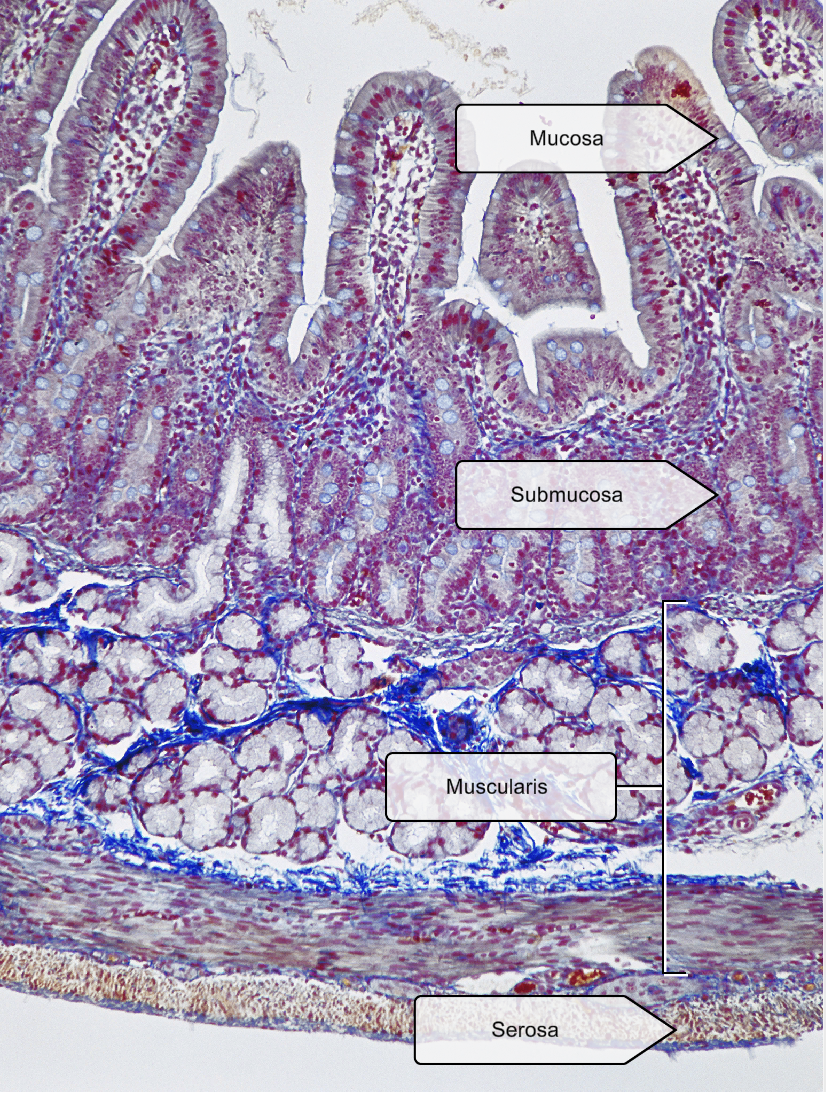

List the layers in the small intestine

Mucosa- ciliated pseudostratified columnar epithelium